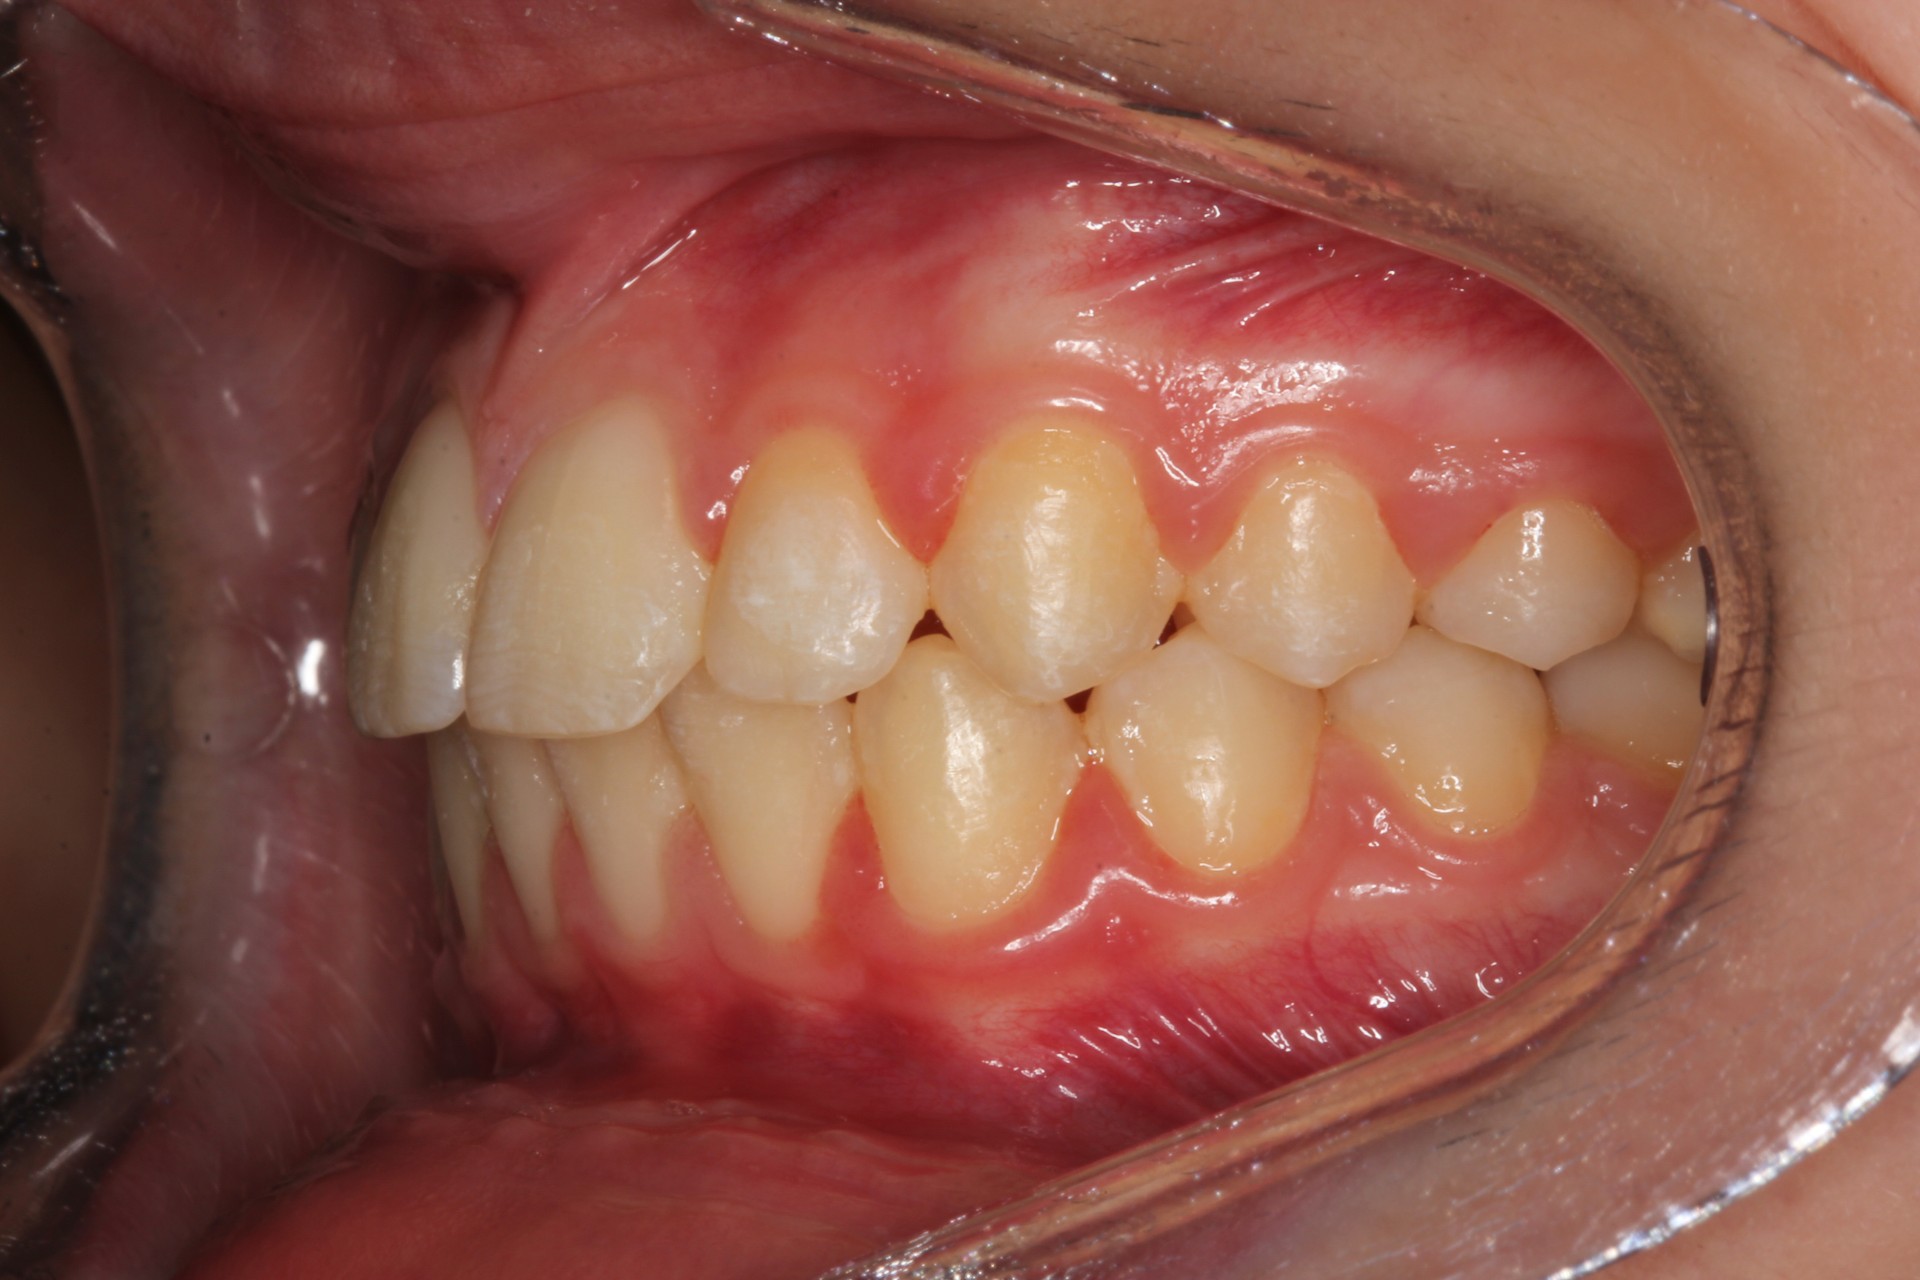

Protruding front teeth and spacing – Child case